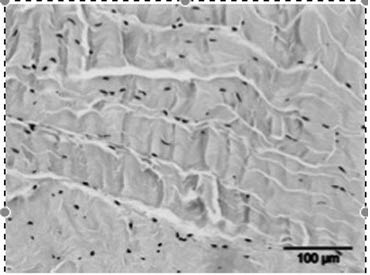

2) Radial

Radial Shock waves produced by a pneumatic hammer are emitted in a

radial way. Thus the intensity of the shock waves is the highest at the surface

(the skin) and gets lower and lower when moving further away from the hammer.

The waves are diverging.

This type of ESWT can be used for the treatment of

superficial structures. Treatment of deeper structures is more difficult because

the diverging shock waves lose lots of energy before getting at the place to be.